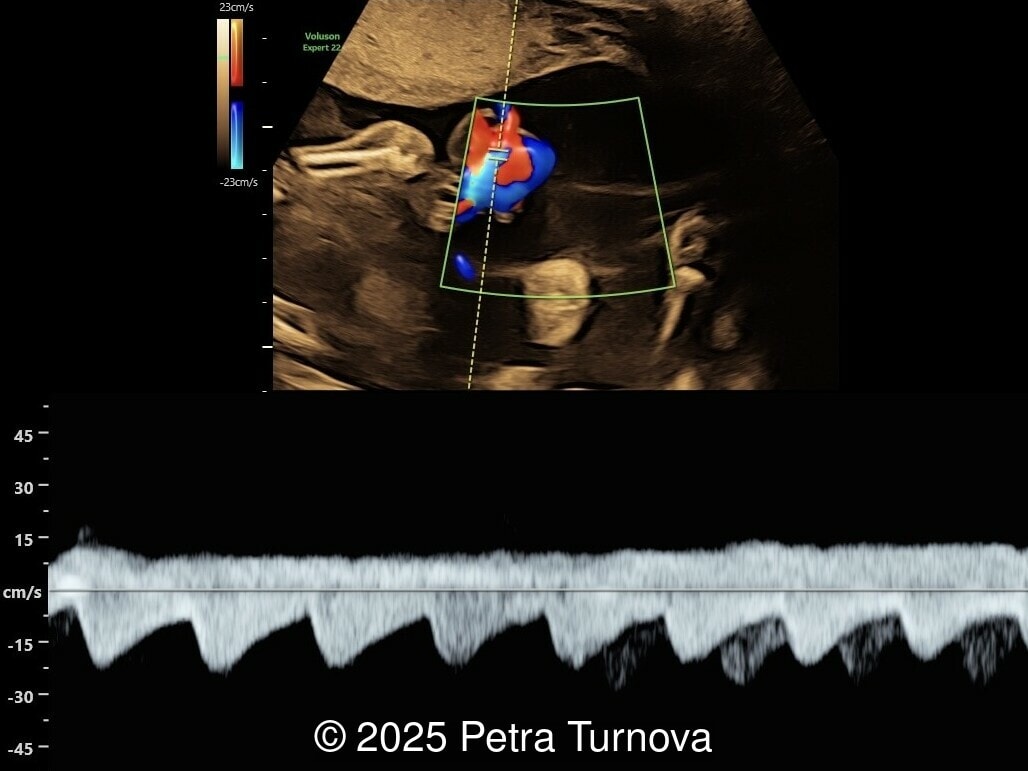

We present a case of cord entanglement. Unfortunately, the pregnancy ended in fetal demise two weeks after our exam.

Our images revealed a monochorionic monoamniotic pregnancy with entanglement of the umbilical cords. Simultaneous doppler registrations of two different heart rates suggests the cord entanglement.  There was no umbilical artery notching to suggest compromised blood flow to the fetuses.  Three-dimensional reconstructions of the umbilical cord entanglement is depicted in the images below.

Cord entanglement can be visualized from the 12-13 weeks of pregnancy. The risk of cord events increases in cases of close cord insertion on the placenta. Some studies have confirmed that intermittent occlusion is associated with neurological morbidity, while prolonged occlusion is fatal. Ultrasound may visualize intertwined umbilical cords. On Doppler flow studies, intermittent or persistent notching of the umbilical artery may be present. This phenomenon is typically observed in abnormal uterine artery flow associated with placental insufficiency and is less frequently seen in umbilical artery flow disorders. Based on physical calculations, it has been shown that notching does not occur unless there is a reduction in tube diameter below 75%. Therefore, notching is present in cases of significant flow reduction.